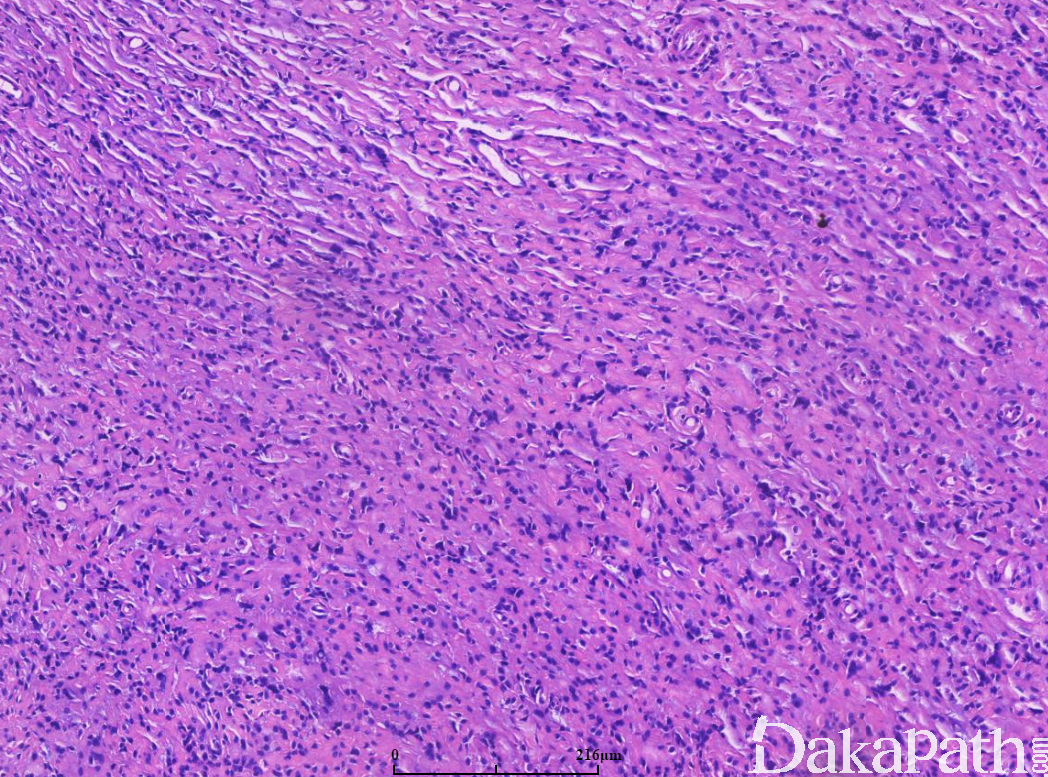

低倍镜下肿瘤呈界限清楚的小叶状结构,小叶内见圆形或多边形细胞紧密排列,间质稀少;